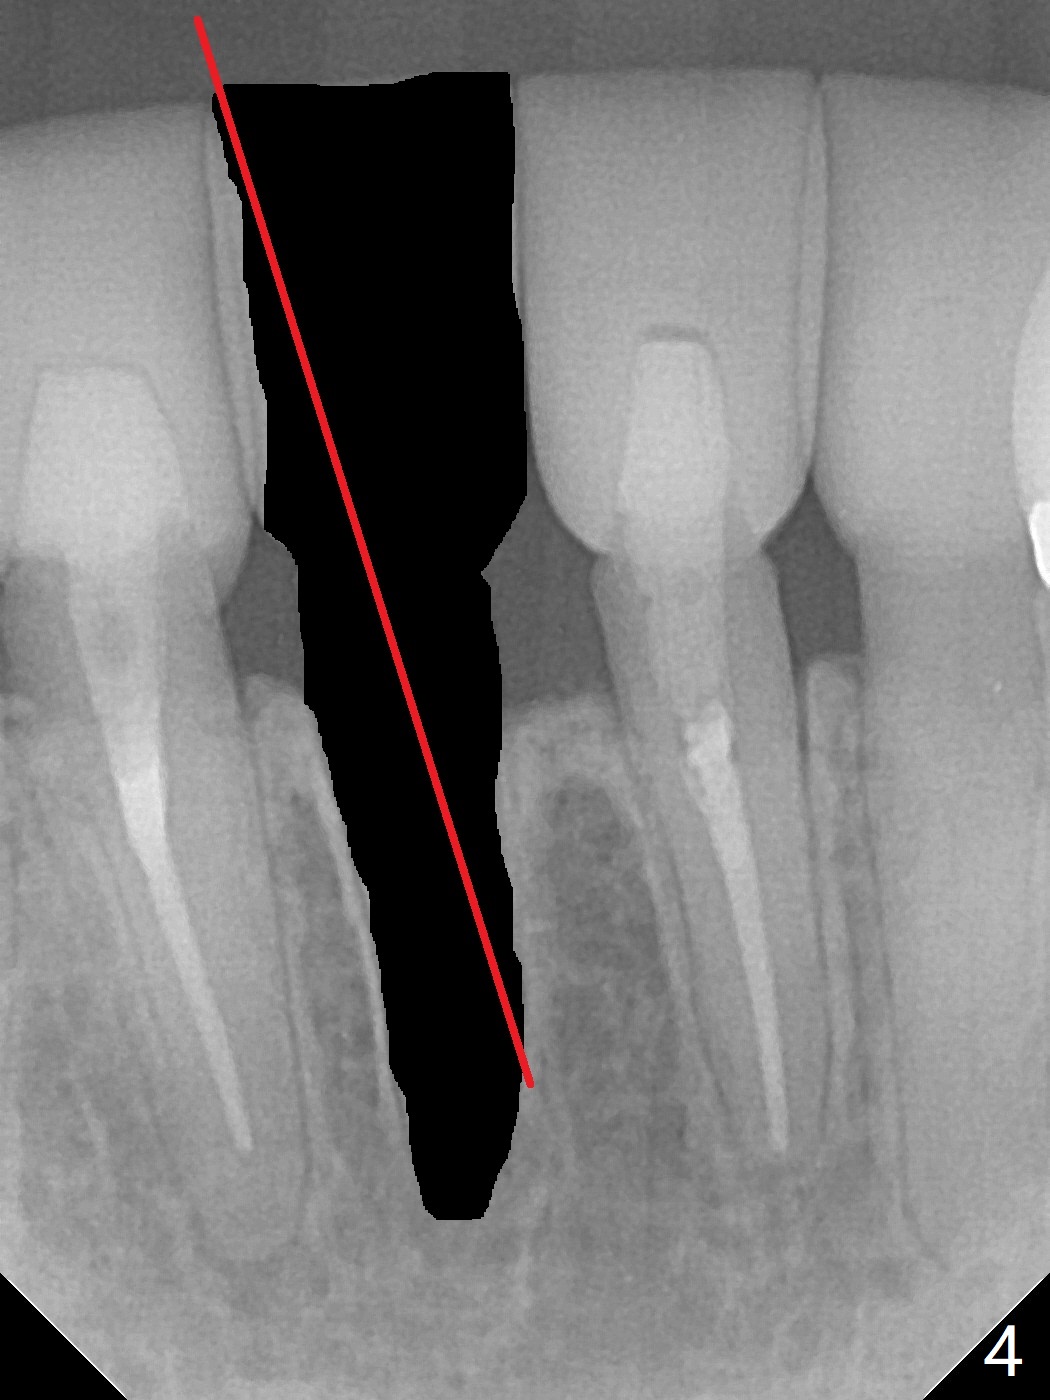

A drawback of implant planning at #25 is not to use a preop PA (Fig.1 (^ fracture line)). The initial trajectory seems to be alright (Fig.2), but a 2.5x14(2) mm implant placed is close to the tooth #26 (Fig.3). In fact the affected tooth is deviated distal; osteotomy should be initiated in the mesial slope of the socket (Fig.4 red line). The final trajectory appears to be perfect (Fig.5). Furthermore the 1st intraop PA should be analyzed carefully (Fig.6). A new osteotomy should be established mesial or the existing one should be moved mesial with Lindamann bur (Fig.7). The distal implant placement may be related to more bone loss in the distal crest 3.5 months postop (Fig.8) and more severe distal papillary recession (Fig.9 *). The bone density increases at the levels of the non-thread and thread portions of the implant (in the original socket) nearly 10 months post cementation (Fig.11 *, <). There is no bone loss 16 months post cementation (Fig.12).